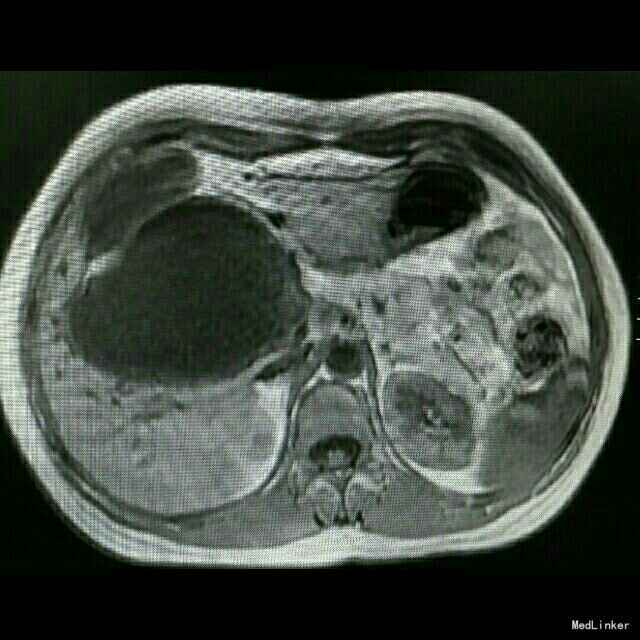

查体:皮肤巩膜轻度黄染 检查:B超示胆总管囊性占位,胆囊增大,肝内胆管扩张。MRCP:先天性肝外胆管囊肿,伴肝内胆管及胰管扩张,胆囊炎,右肝血管瘤可能。TB 65 umol/L;DB 41 umol/L; ALT 137U/L;AST74 U/L ;γ-GT366 U/L术后恢复正常。肿瘤指标正常。

诊断:先天性胆总管囊肿,慢性胆囊炎。 治疗:行胆总管囊肿切除+胆囊切除+胆道空肠Roux-en-y吻合术。术中腹腔未见积液,胆总管大小越25*8.5cm,囊壁较厚,胰头部受压明显,胆囊10*6*5cm。沿胆囊底打开胆囊浆膜,逆行游离至胆囊管汇入处,结扎胆囊动脉,打开肝十二指肠韧带,沿胆总管囊肿游离囊肿,保护肝动静脉及门静脉,向下游离至胰内胆管,于囊肿下端切断胆总管,结扎残端。向上游离至肝门部,于左右肝管汇合处离断,完整切除囊肿。距屈氏韧带25cm直线闭合器断空肠,游离远端空肠系膜行肝总管远端空肠段侧吻合。距胆肠吻合口远端45cm处,空肠与近端空肠残端以直线切割闭合行空肠侧侧吻合。间断缝合残端,吻合口放置引流管,关腹。术后加强白蛋白对症支持治疗,术后第5日开始进食流质。病理回报慢性胆囊炎。